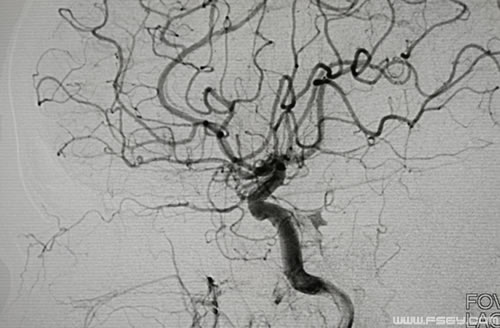

造影显示颈内动脉破裂

血管造影显示右侧颈内动脉破裂,张主任果断的封堵了瘘口,同时保持右侧颈内动脉通畅,患者鼻腔出血停止,手术顺利结束,术后安排到重症医学科继续抢救。目前,患者病情稳定已转到神经外科普通病房。